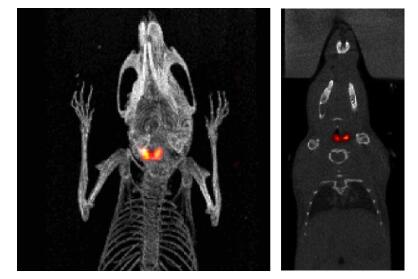

圖 3. PET-PDAC 小鼠模型(12.11MBq(327µCi) [18F]FDG, 采集時(shí)間: 10min) , 研究胰腺腫瘤, 發(fā)現(xiàn)腎臟也有轉(zhuǎn)移【1】 。

圖 8. 來自肺腫瘤模型研究的小鼠的 PET(左)和 PET/CT( 右) 圖像, 6.47MBq( 175μ Ci)

[18F]FDG, 15min PET【1】 【2】 。